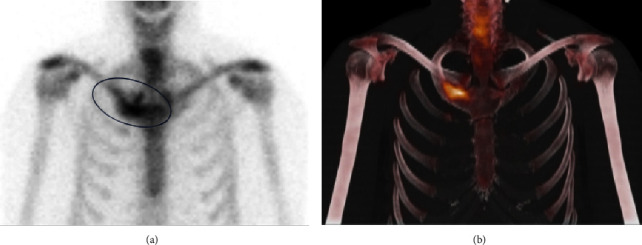

SAPHO综合征是一种罕见的骨、关节和皮肤炎症性疾病,因出现滑膜炎、痤疮、脓疱病、骨质增生和骨炎而得名。SAPHO综合征的标志包括骨关节和皮肤表现,然而,与炎症性肠病(特别是克罗恩病)的罕见关联已被记录。关于SAPHO综合征与炎症性肠病(IBD),特别是溃疡性结肠炎(UC)之间关系的文献仍然有限。我们报告一个不寻常的病例SAPHO综合征患者UC。胸部x线及MRI显示右侧第一肋骨及邻近胸骨肿大。骨显像显示肋软骨连接处骨质增生和强直,骨活检显示骨和肋软骨反应性,未见感染或恶性肿瘤。使用唑来膦酸4个月后症状完全缓解,无明显不良反应。SAPHO综合征在IBD患者中诊断罕见,在UC患者中更是如此,这可能是由于SAPHO综合征的临床异质性以及与IBD的肠外表现重叠导致的漏诊。我们的治疗方法为UC中SAPHO综合征的诊断和治疗文献提供了重要的数据。

SAPHO syndrome, a rare inflammatory disorder of bone, joints, and skin, is named based on the presence of synovitis, acne, pustulosis, hyperostosis, and osteitis. The hallmark of SAPHO syndrome includes osteoarticular and dermatologic manifestations, however, rarer associations with inflammatory bowel disease (particularly Crohn's disease) have been documented. The literature on the relationship between SAPHO syndrome and inflammatory bowel disease (IBD), especially ulcerative colitis (UC), remains limited. We report an unusual case of SAPHO syndrome in a patient with UC. Chest x-ray and MRI showed enlargement of the right first rib and adjacent sternum. Bone scintigraphy revealed hyperostosis and ankylosis of the costochondral junction, and bone biopsy revealed reactive bone and costal cartilage without findings of infection or malignancy. Complete resolution of symptoms was achieved 4 months after starting zoledronic acid without significant adverse events. The diagnosis of SAPHO syndrome in IBD patients is rare, even more so in UC patients, likely attributable to underdiagnosis given the clinical heterogeneity of SAPHO syndrome and overlap with the extra-intestinal manifestation of IBD. Our treatment approach provides critical data to the underreported literature on diagnosis and managing SAPHO syndrome in UC.